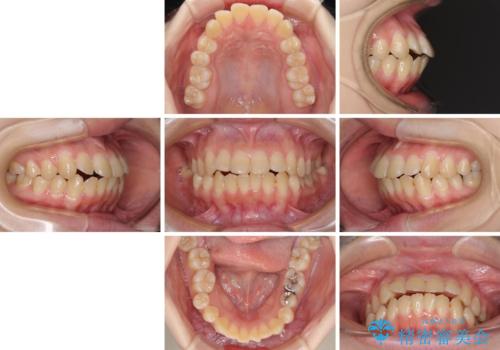

- 上下前歯が前方に飛び出しているとのことで来院された患者様です。

上下左右第一小臼歯4本を抜歯して、積極的に口元を引っ込めるよう、ワイヤー装置にて矯正治療を行うこととしました。

口元の突出感は著しく改善され、横顔の印象が大きく変化しました。